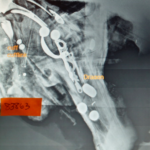

An X-ray shows the cufflink and dragoon on what is believed to be a pirate skeletal remains found off Cape Cod, Massachusetts.